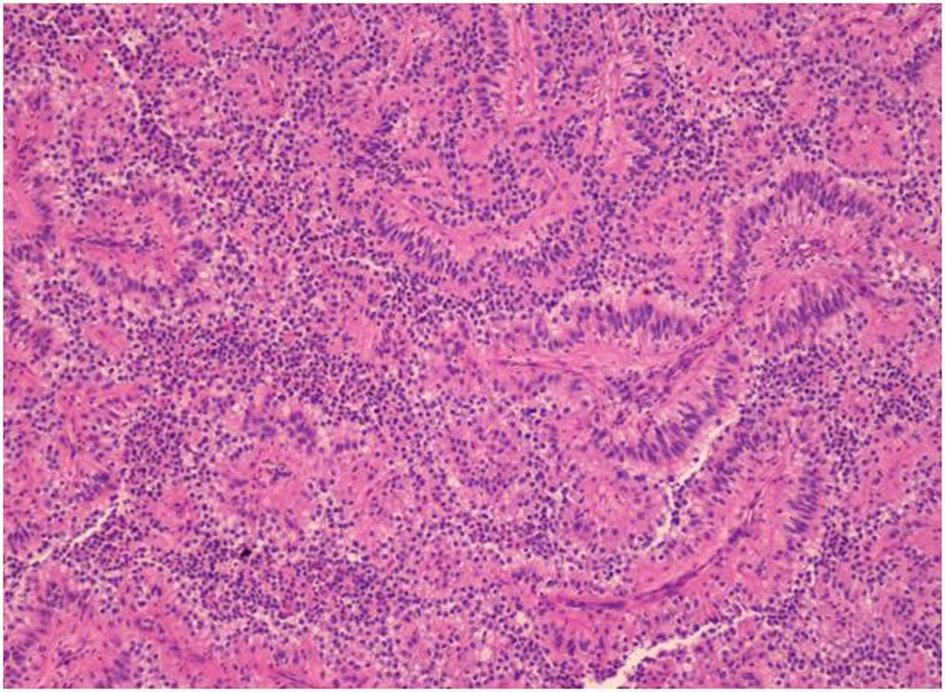

At that time, preliminary diagnosis was metastatic adenocarcinoma of lung cancer as the primary site. The physician started treatment in October 2008 with 2 cycles of palliative chemotherapy, carboplatin and paclitaxel. However, the disease progressed. CT chest and abdomen in January 2009 revealed left superior mediastinal node slightly increased and the mass at the pararenal region and necrotic node, paravertebral node were about the same. Treatment was switched to 2nd line with cisplatin and Etoposide for 2 cycles. After the 2nd cycle, he lost follow up for 1 year because of chemotherapy side effect. A year later, the patient went to Chulabhorn hospital for a second opinion. The pathology of lymph node was evaluated and formed to be metastatic papillary adenocarcinoma (Fig. 4). Further immunohistochemistry for TTF-1, Thyroglobulin, CD7 and CD20 were all negative.

![]() Click for large image | Figure 4. Hematoxylin & Eosin stain (H&E stain) of biopsied left supraclavicular lymph node showing lymph node with metastatic epithelial neoplasm arranging in papillary growth pattern. The neoplastic cells have enlarged pleomorphic and prominent nuclei, eosinophilic and clear neoplasm. |

CD10 AE1/AE3, Vimentin and RCC were positive, suggesting that the disease was renal cell carcinoma. Therefore, the patient was diagnosed with papillary cell type metastatic renal cell carcinoma without renal mass as primary site. In the present time, the patient is doing well with stable disease and is being treated with Sunitinib cycle15th (last September 2012). Follow-up CT scan still demonstrated no primary kidney lesion.